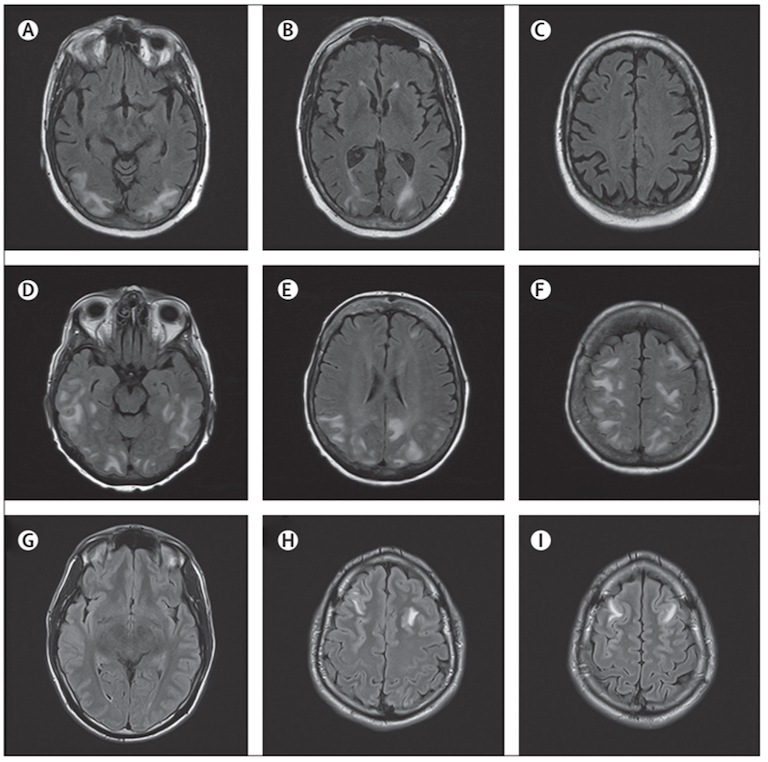

A ulteriore approfondimento, è stata eseguita una RM encefalo con riscontro di multiple aree di alterato segnale a livello corticale localizzate bilateralmente agli emisferi cerebrali con reperto prevalente a destra in regione frontale e parietale e con coinvolgimento, a questo livello, della sostanza bianca e in assenza di segni di impregnazione patologica di mezzo di contrasto, reperti radiologici compatibili con leucoencefalopatia posteriore reversibile (PRES).

Approfondendo lanamnesi con i caregiver è emerso un consumo abituale e continuativo di liquirizia da parte del bambino negli ultimi mesi prima del ricovero. Inoltre, alla misurazione della PA durante la degenza, è stata riscontrata unipertensione arteriosa di stadio II (PA >95esimo percentile) senza danno dorgano a livello cardiologico, renale e retinico. Lipertensione riscontrata ha necessitato di politerapia antipertensiva con ACE-inibitore (captopril), diuretico (acetazolamide) e calcio-antagonista (amlodipina) per ottenere un buon controllo pressorio. Inoltre, il paziente non ha più presentato episodi critici ed è stato riscontrato un netto miglioramento del quadro radiologico alla RM encefalo eseguita a 14 giorni di distanza.

La sindrome da leucoencefalopatia posteriore reversibile (PRES) è una sindrome clinica e radiografica a eziologia eterogenea caratterizzata da sintomi neurologici acuti di disfunzione cerebrale associati ad anomalie caratteristiche al neuroimaging nella sostanza bianca e grigia cerebrale posteriore (Figura).

Al neuroimaging (preferibilmente RM con immagini pesate in diffusione) si riscontra tipicamente un edema vasogenico localizzato bilateralmente a livello della sostanza bianca negli emisferi cerebrali posteriori, in particolare nelle regioni parieto-occipitali, ma linteressamento è variabile3.